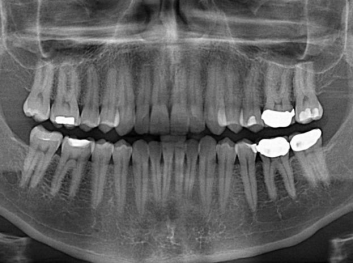

在體外測(cè)試中,材料刺激干細(xì)胞進(jìn)入牙本質(zhì)的增殖和分化速度,促進(jìn)形成牙齒骨組織。研究人員認(rèn)為,一旦材料在受損牙齒中應(yīng)用,這些干細(xì)胞可以自動(dòng)修復(fù)來自填充物上的損壞。在本質(zhì)上,該生物材料將使牙齒自愈。

在未來,Adam Celiz說,可再生材料能制成各種填充物以便受損牙齒的自身治愈,降低補(bǔ)牙失敗率,甚至?xí)蟛糠秩藢?duì)根管治療的需要。